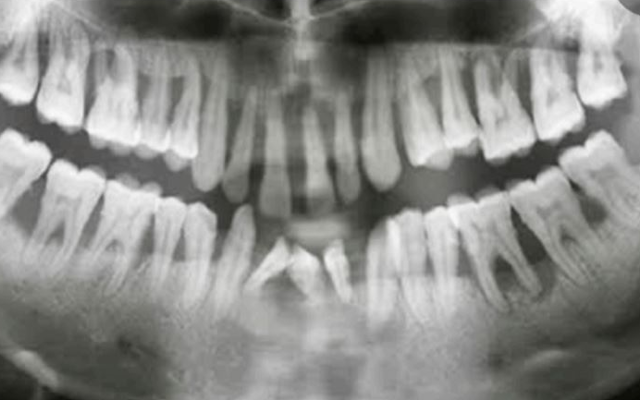

Orthopantomogram (OPG):

The OPG will provide a view of your entire mouth, including the surrounding jawbones and a view of the sinuses and the lower part of the eye sockets (Fig 19B). It is a very useful x-ray for the assessment and monitoring of periodontal conditions. They provide a lot of information at a very low dose of radiation exposure. The OPG is not as sharp in focus as an intraoral x-ray, so intraoral x-rays may also be required. Some periodontists will take an OPG with their own machine. Others will refer you to a medical radiology clinic for the OPG.